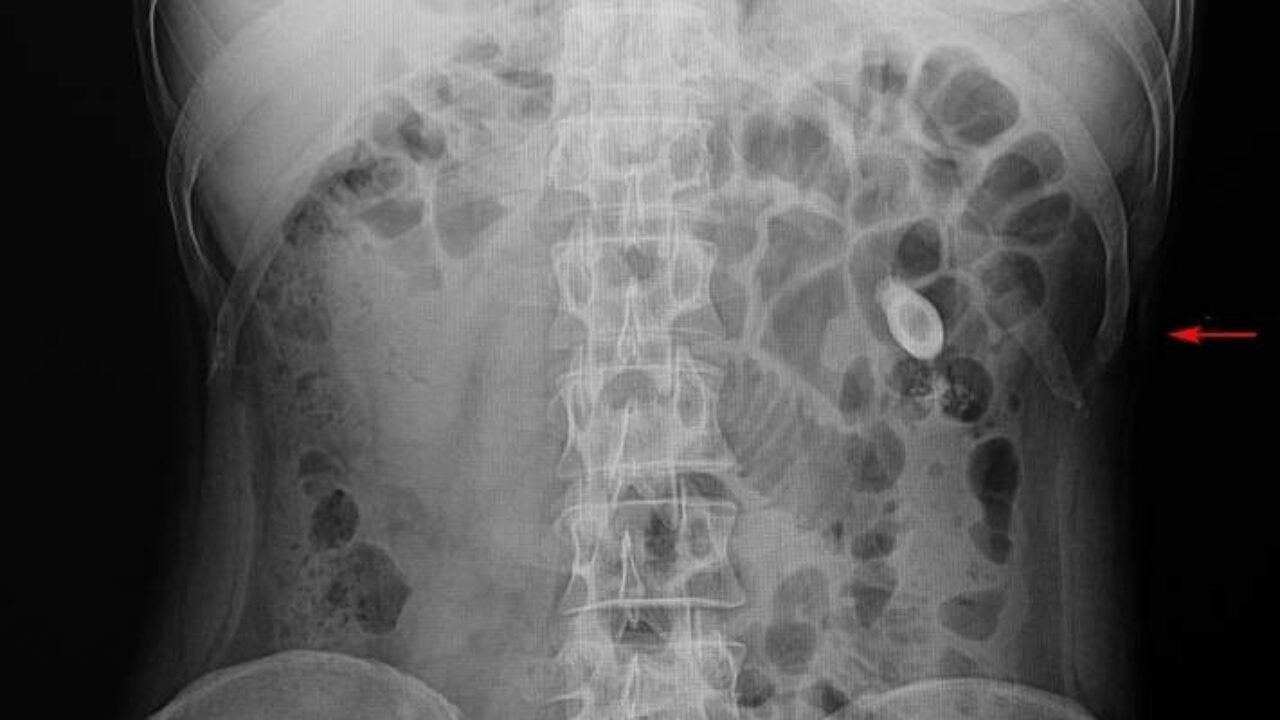

Evrakları karışan ve safra kesesi ameliyatına girmek üzereyken son anda durumu fark edilen Murat Çataldaş, "Apandisitimden iki kere ameliyat oldum, yanlışlıkla safra kesesinden de olacaktım. Babam yetişti de az kalsın giriyorduk ameliyathaneye. Odalar karışmış, o yüzden. Benim yatacağım bölüm farklıydı ama oda olmadığı için beni aşağıda başka bir bölüme yatırmışlar. Öyle olunca yukarıdaki odayla dosyalar karışmış, doktor bey tabii açıklama yaptı sonra. Doktorla helalleştik, sorunu çözdük. Devamlı kontrole de gidiyorum, doktorla aramız iyi yani. O da güldü, ’senin işin Kemal Sunal filmine döndü’ dedi, şakalaştık. Şu an iyiyim kontrollerime gidip geliyorum, bir tek böbrek taşım var o kadar" dedi.